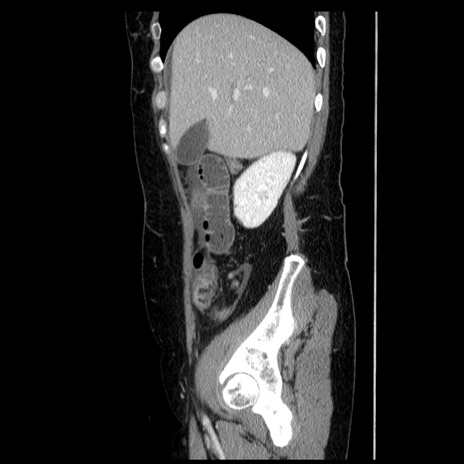

症例6(矢状断像)

【症例】50歳代女性

【主訴】下腹部痛

【現病歴】本日朝より下痢2回あり。 昼食を食べた後、嘔吐3回、下腹部痛認め、症状軽快せず、当院救急搬送。

最終食事:本日昼(生ものなし)。 昨日の夜、刺身を食ぺたとのこと。周囲に同様の症状の者なし。普段、排便は毎日あるとのこと。

【既往歴】卵巣癌術後(8年前に当院で卵巣摘出)

【身体所見】 意識清明、腹部:平坦、腸蠕動音→、やや硬、下腹部自発痛・圧痛あり、反跳痛あり、筋性防御なし。

【データ】WBC 16000、CRP 0.01